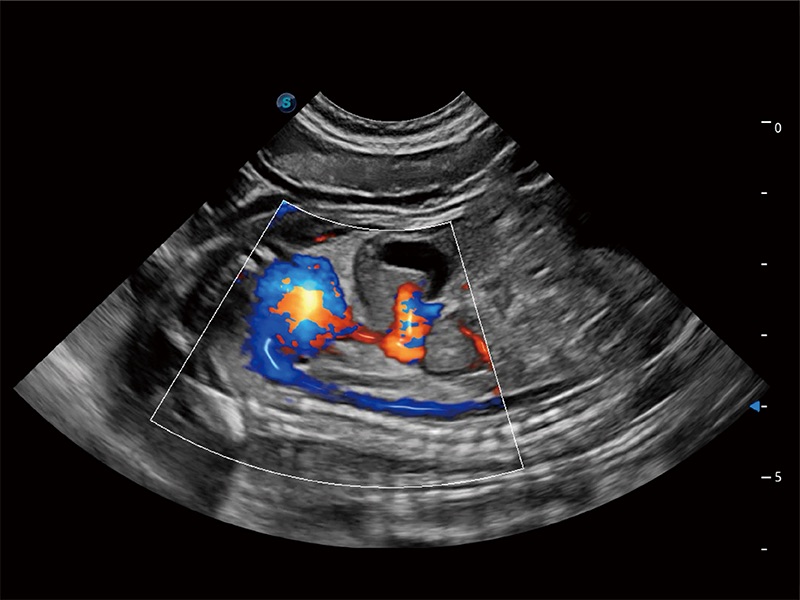

(犬)二腔心血流